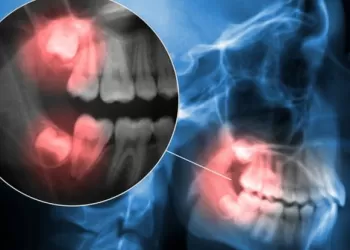

Dental Radyoloji

Periapikal Film Nasıl Çekilir?

Periapikal Film Nasıl Çekilir? Diş köklerindeki ve çevre dokulardaki problemleri detaylı görmek için röntgen.